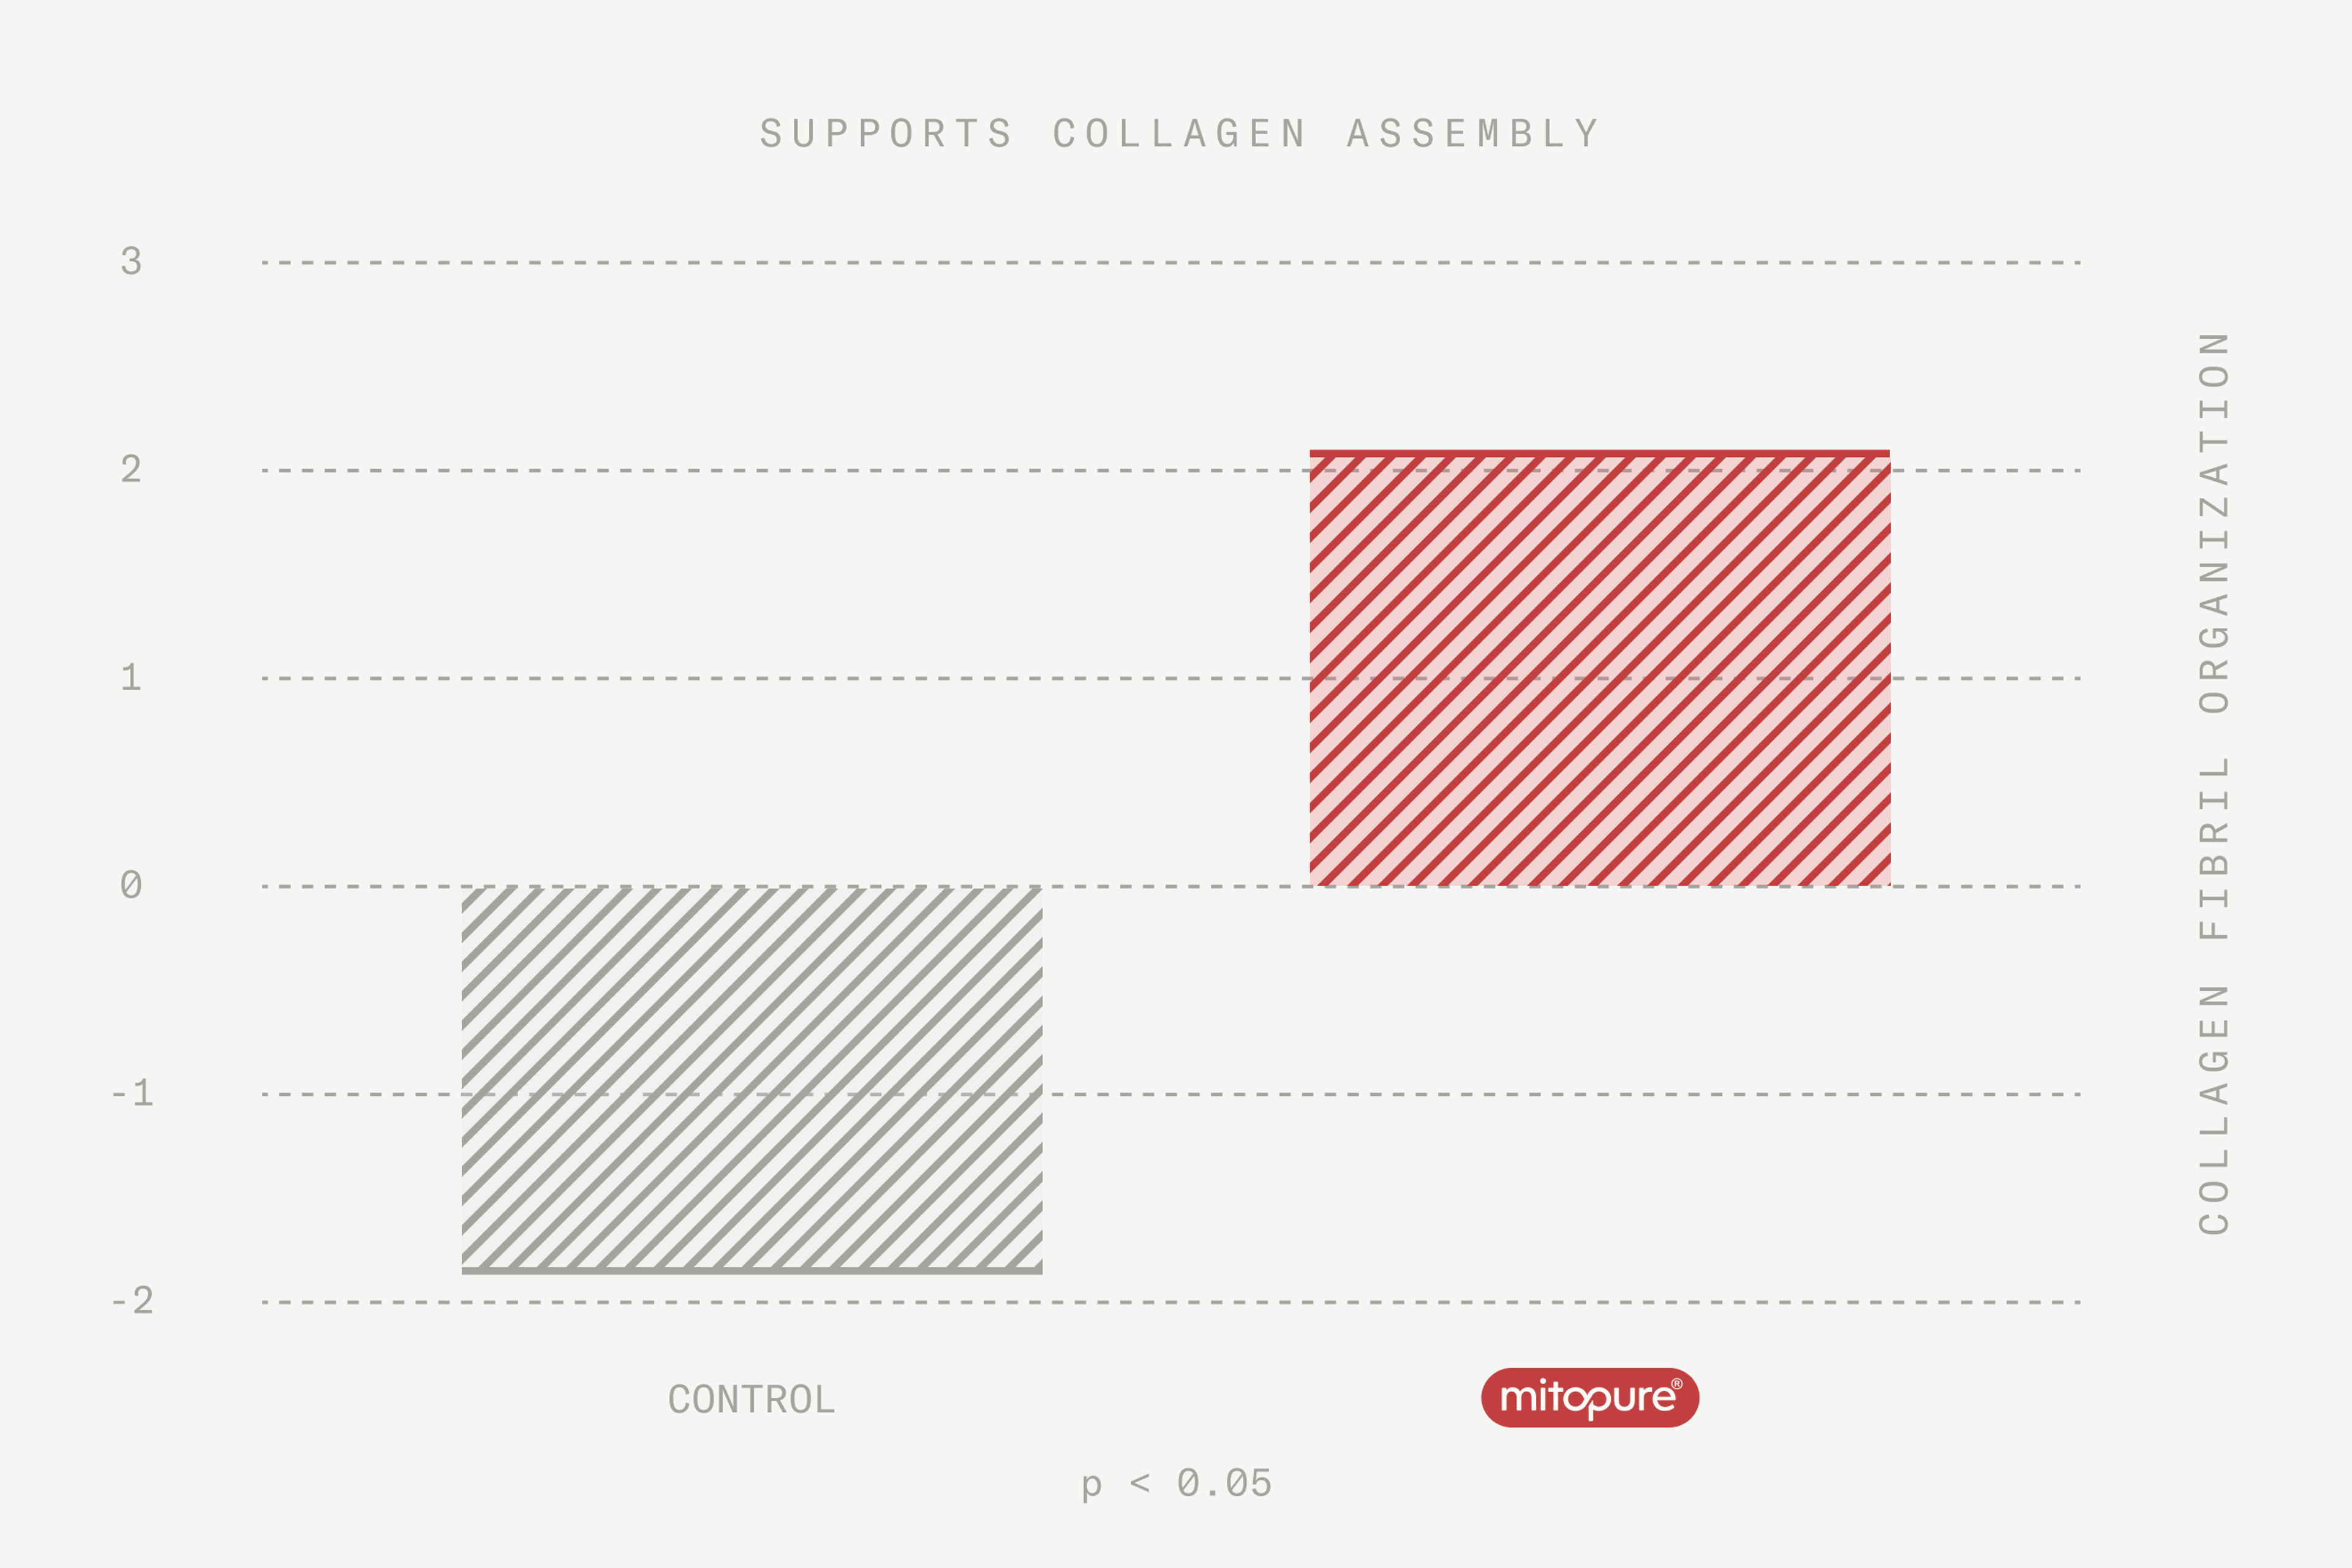

It is clinically proven to support collagen production and assembly, and protect skin from environmental damage (photo-aging)

Mitopure® is clinically proven to help fight off both intrinsic and extrinsic aging factors by supporting collagen assembly and protecting skin from environmental damage (photo-aging).

What’s the evidence? Mitopure® is clinically proven to support the processes inside the skin cells that power up collagen assembly and formation.